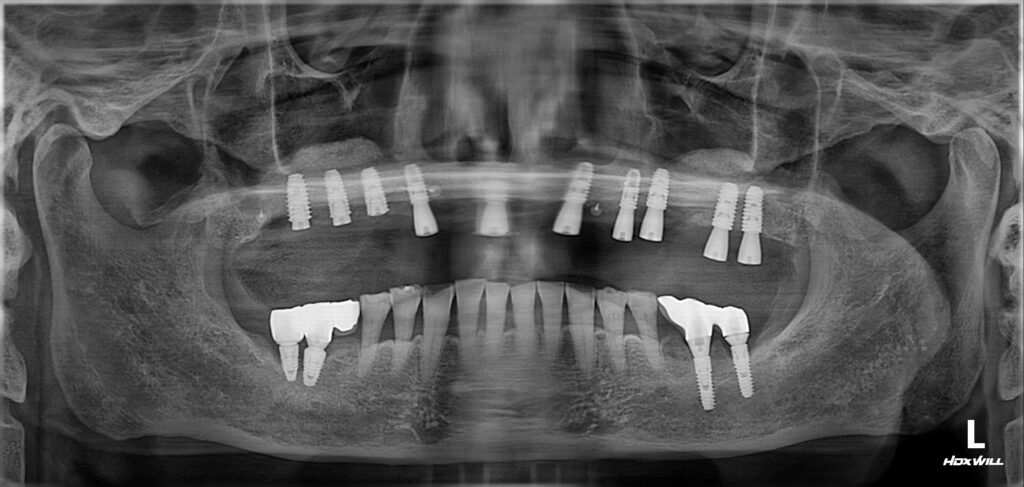

전체 임플란트 수술 완료

양쪽 상악동 거상술을 포함해서 수술을 완료했습니다.

보셔서 아시겠지만 아주 좋은 위치와 간격으로 임플란트가 식립된 것을 볼 수가 있습니다.

이렇게 원칙을 잘 지켜서 섬세하게 식립한 임플란트는 추후에 오랫동안 튼튼하게 제 기능을 할 가능성이 매우 높습니다.

상악동 거상술이란? –> https://brplant.co.kr/2784/